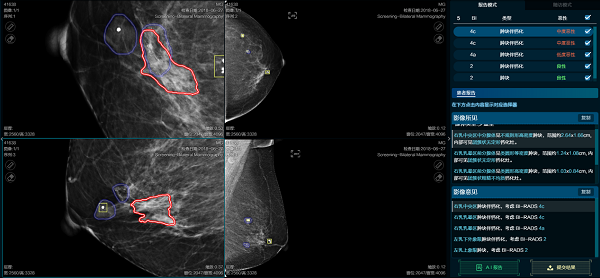

5月14日,医准智能正式对外发布乳腺钼靶智能检测3.0系统。升级后的系统病灶检出率进一步提高达到93%、良恶性准确率达到94%,实现了20秒完成乳腺全病种分析,覆盖乳腺钼靶全病种:肿块、钙化、肿块伴钙化、乳头回缩、皮肤增厚、腺体类型、淋巴结肿大,检测腺体类型并预测病灶良恶性;此外,系统自动生成BI-RAIDS分级和报告文本、自动计算钙化的数量和肿块大小,自动进行轴位和斜侧位配准。

5 月 14 日,医准智能正式对外发布乳腺钼靶智能检测 3.0 系统。升级后的系统病灶检出率进一步提高达到 93%、良恶性准确率达到 94%,实现了 20 秒完成乳腺全病种分析,覆盖乳腺钼靶全病种:肿块、钙化、肿块伴钙化、乳头回缩、皮肤增厚、腺体类型、淋巴结肿大,检测腺体类型并预测病灶良恶性;此外,系统自动生成 BI-RAIDS 分级和报告文本、自动计算钙化的数量和肿块大小,自动进行轴位和斜侧位配准。

BI-RADS分级更为精准,一改以往病灶性质判别偏恶性,BI-RADS 分级过高的不足。

诊断结论更符合医生需求,各项指标的改进,使 AI 计算结果、报告结论更符合医生思路及标准。

3.0 版本不仅实现病灶的精准检出,而且在恶性病灶检出、BI-RADS 分级准确、病灶匹配上表现优异